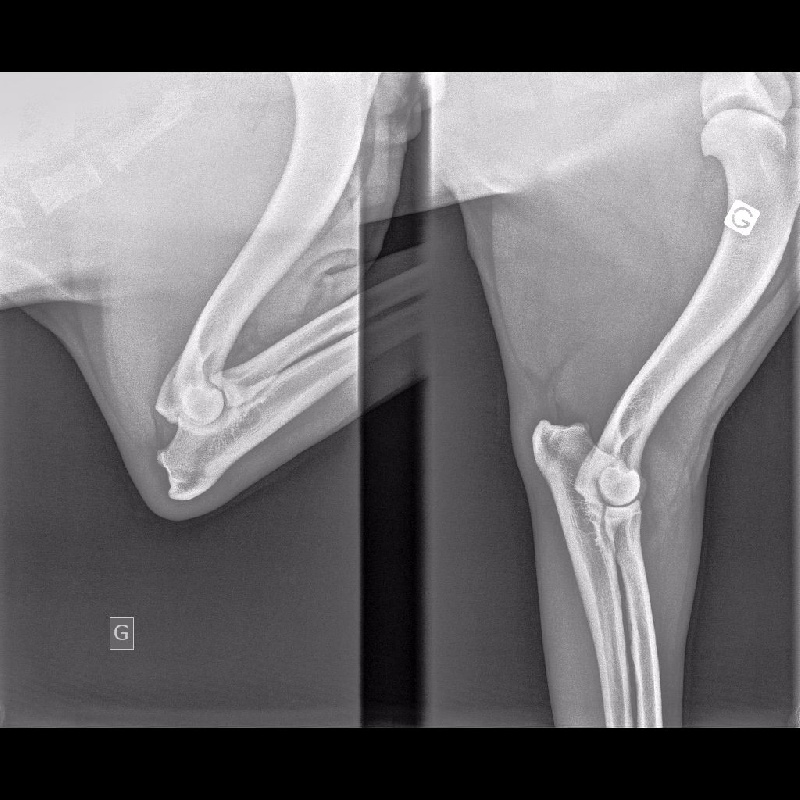

COUDES